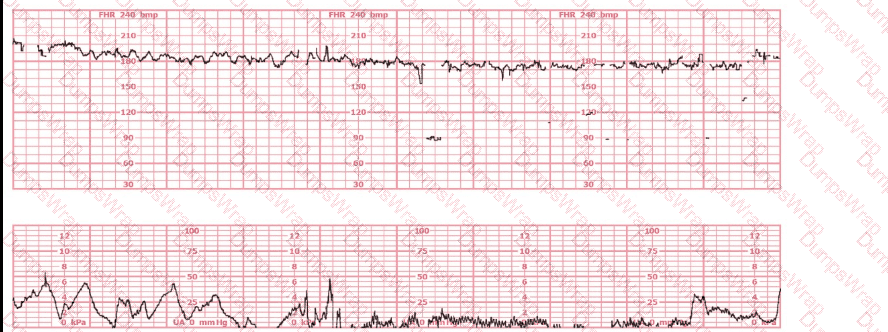

The decelerations seen in the fetal monitoring tracing shown are best described as:

Options:

Early

Late

Variable

Answer:

CExplanation:

Comprehensive and Detailed Explanation From Exact Extract–Based NCC C-EFM References:

Accurate classification of decelerations requires evaluating their shape, onset, nadir, recovery, relationship to contractions, and variability characteristics. NCC uses the NICHD standardized definitions, reinforced across AWHONN, Miller’s Pocket Guide, Menihan, Simpson, and Creasy & Resnik.

Key features in this tracing:

Abrupt onsetThe FHR drops rapidly from baseline to nadir in less than 30 seconds—this is the defining hallmark of a variable deceleration per NICHD.

Sharp V-shape and deep amplitudeThe tracing shows steep descents and ascents, characteristic of cord compression–type variable decelerations.

Inconsistent timing with contractionsThe decelerations do not begin at the start of contractions (as early decelerations would) and do not consistently begin after the peak of contractions (as late decelerations would). Variable decelerations can occur before, during, or after a contraction—exactly what is demonstrated here.

Rapid return to baselineAnother core feature of variable decelerations in NICHD/NCC definitions.

No uniform contraction relationshipEarly decelerations are symmetrical and mirror contractions. Late decelerations begin after the peak of the contraction. This strip does not match either pattern.

Differentiation per NCC-aligned definitions:

Early Decelerations:Gradual onset (>30 sec), nadir mirrors contraction peak, shallow, uniform.Not present.

Late Decelerations:Gradual descent, nadir after contraction peak, smooth shape.Not present.

Variable Decelerations:Abrupt onset (<30 sec), variable timing, sharp V-shape, rapid recovery, often with shoulders.Exactly matches the tracing.

Therefore, according to NICHD/NCC criteria, the decelerations shown are variable decelerations.

The pattern on the fetal heart rate tracing shown is likely due to

fetal head compression

placental insufficiency

umbilical cord compression

Comprehensive and Detailed Explanation From Exact Extract Sources:

The tracing demonstrates an abrupt-onset, sharp, V-shaped deceleration, occurring simultaneously with or slightly after a contraction—classic for variable decelerations, which are caused by umbilical cord compression.

According to AWHONN Fetal Heart Monitoring Principles & Practices, variable decelerations are defined by:

“Abrupt decreases in FHR below baseline of at least 15 bpm, lasting at least 15 seconds and less than 2 minutes.”

“Most commonly associated with umbilical cord compression, whether transient or recurrent.”

Physiology reference (Simpson & Miller, Pocket Guide):

Compression of the umbilical vein causes a brief acceleration.

Compression of the umbilical arteries triggers a vagal response, producing a rapid deceleration.

This creates the characteristic sharp ‘V’, ‘U’, or ‘W’ shape on the monitor.

Placental insufficiency (Choice B) produces late decelerations, which are gradual, not abrupt.

Fetal head compression (Choice A) produces early decelerations, which mirror contractions and have a gradual pattern.

Thus, the tracing is most consistent with variable decelerations caused by umbilical cord compression.